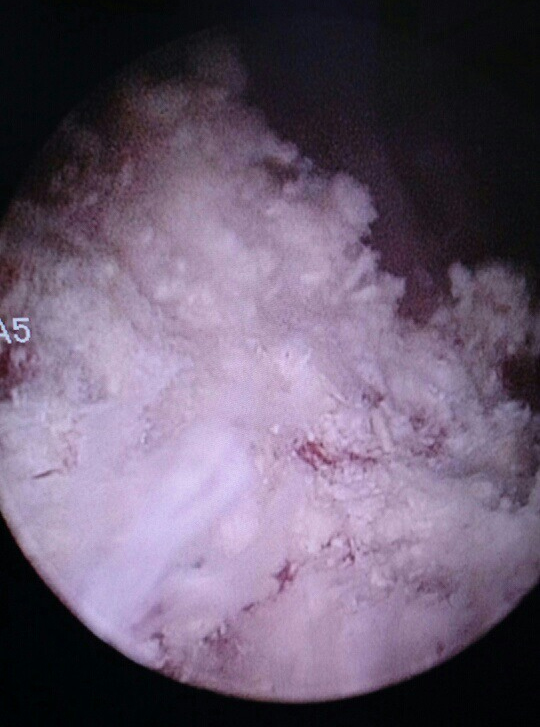

Our patient was a 65-year-old man who had ultra-low anterior resection and chemo-radiotherapy for rectal cancer. On follow-up computed tomography (CT) scan of the abdomen and pelvis a year later, he was found to have a bladder mass (Fig. 1). He subsequently underwent elective TURBT and received intravesical mitomycin C (40 mg diluted in 40 ml of saline 0.9%) within 6 h post-operatively. Histology revealed non-invasive, low-grade TCC. Three weeks later, a follow-up CT scan of the abdomen and pelvis was performed for routine follow-up of the rectal cancer; this scan incidentally detected calcification of the bladder wall at the surgical resection site (Fig. 1). He was asymptomatic. Cystoscopy and cystolitholapaxy was then performed for presumed bladder calculi, approximately three months after the TURBT. Extensive stone-like, whitish calcification of the bladder wall at the surgical resection site was found (Fig. 2), not merely slough or soft tissue material. These lesions were further resected down to the detrusor muscle layer as the material was not amenable to washout. Histology (Fig. 3) revealed chronic inflammation of urothelium and fragments of refractile, hard-edged material which was found to be made up of calcium phosphate. There were no features of malignancy. He had normal serum calcium and phosphate levels and no known history of exposure to tuberculosis or schistosomiasis or travel to Africa, Middle East or South East Asia. He had no symptoms of interstitial cystitis. Aside from the history of rectal cancer and associated therapy, he had no other relevant oncological history. He received intravenous fluorouracil, folinic acid and oxaliplatin adjuvant chemotherapy for rectal cancer with the final cycle administered more than 12 months prior to this diagnosis of bladder wall calcification. He never received any intravesical therapy prior to the single dose of mitomycin C administered after the initial TURBT. In view of the rapid onset and localized involvement of the resection site, the bladder wall calcification was most likely secondary to intravesical mitomycin C treatment. Since this episode, there was no further recurrence or long-term consequence. Thus, no further treatment was required aside from routine cystoscopy for follow-up of non-muscle invasive, low-grade bladder cancer.

Figure 1. Axial view of CT scan showing a bladder mass (blue arrow in Figure 1A) on the posterior wall (A) and calcification (blue arrow in Figure 1B) on the posterior bladder wall at the resection site (B).